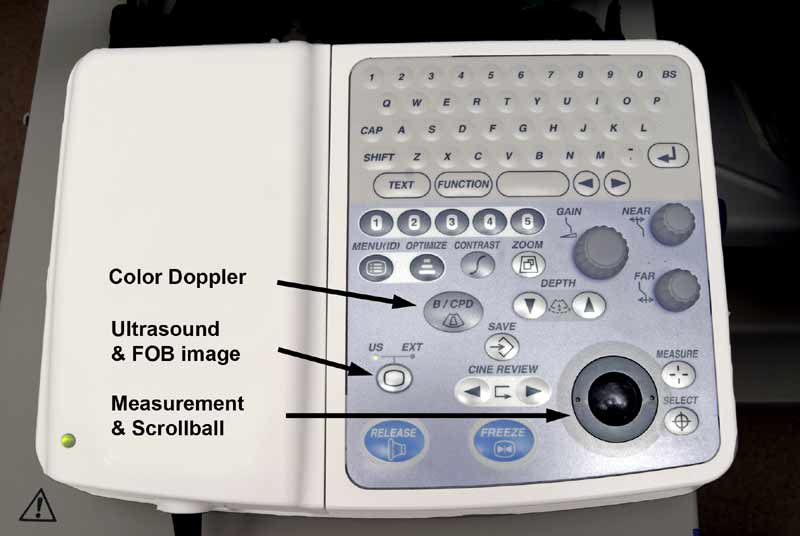

Figure 1: Olympus BF-UC160F-OL8 endobronchial ultrasound bronchoscope. Saline filled syringe attached to balloon inflation port.

The EBUS bronchoscope (BF-UC160F-OL8; Olympus America Inc., Center Valley, PA) is similar in dimensions to a standard adult fiber optic bronchoscope. The 6 mm diameter scope has a curvilinear ultrasound (US) probe at its distal end which provides a 50 degrees linear continuous B-mode ultrasound image, with color Doppler capability to aid identification of vascular structures (Figure 1). Proximal to the US probe, and at 30 degrees to the long axis of the bronchoscope, are a fiber optic lens and a biopsy channel, through which a 22-G biopsy needle can be passed (NA-201SX-4022; Olympus America Inc., Center Valley, PA) (Figure 2). A disposable latex balloon is placed over the US probe, which is inflated with sterile water to provide a fluid interface between the probe and the tracheal wall.

A 20 cc syringe filled with sterile water is attached to the balloon channel of the scope using an arterial line with a stopcock, and the channel filled with water (Figure 1). A disposable latex balloon is then carefully placed over the ultrasound probe, using the provided applicator and then inflated with saline. All air bubbles should be evacuated from the balloon prior to sealing it in place, which is easily done by applying pressure to the distal circular lip of the balloon with the tip of a gloved finger. Silicone spray should then be used to lubricate the scope.

In the United States EBUS is usually performed under general anesthesia with use of a laryngeal mask airway and intravenous anesthesia [1] (Figure 3). This permits evaluation of the upper paratracheal nodes which may not be accessible if an endotracheal tube is used. A standard fiber optic bronchoscope is first used to determine anatomy, clear secretions and ensure absence of endobrochial disease that might make EBUS superfluous. The EBUS scope is then advanced into the trachea. When manipulating the bronchoscope through the vocal cords it is important to note that the visualized image is at 30 degrees to the long axis of the bronchoscope. The balloon is then inflated so that a small crescent of it may be seen at the bottom of the fiber optic image (Figure 4). The image is inferior to that of a standard bronchoscope because of the smaller diameter of the fiber optic system required to accommodate the biopsy channel and ultrasound. The [US-EXT] button on the ultrasound processor (EU-C60; Olympus America Inc., Center Valley, PA) toggles between the fiber optic and ultrasound views (Figure 5). Use of 2 monitors or a single monitor with picture-in-picture display is useful.

The easiest place to start ultrasound imaging is generally the right main bronchus and subcarinal areas. Pass the scope to the right side of the carina with the probe facing anteriorly and apply to the anterior wall of the RMB. This will bring into view the right main pulmonary artery. Vascular structures appear hypoechoic and pulsatile, and are usually readily discernable without using the color Doppler. If doubt persists flow within can be confirmed by switching to the Doppler overlay (B/CPD; Figures 5 and 6). Turn the scope 90 degrees counter-clockwise. This allows visualization of the subcarinal area from the right side. By moving the scope in and out the level 7 subcarinal node can usually be identified. If not, repeat this procedure in the LMB turning the scope 90 degrees clockwise instead. Once the subcarinal nodes are visualized it is relatively easy to identify other landmarks, by correlating anatomical location with the ultrasound image. It is useful to attempt to map out all nodes that you wish to biopsy first, before needle tract bleeding confounds the fiber optic image. The size of the node can be measured by freezing the US image [Freeze] and using the [Measure/Select] button and cursor scroll ball (Figures 5 and 7).